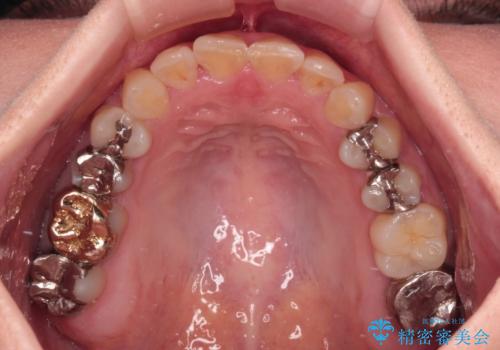

気になる歯列不正とむし歯を治療 インビザライン治療と虫歯治療

- 治療途中の奥歯の治療継続と、前歯のデコボコを気にして来院された患者様です。

根管治療まで終了している歯は症状がないため、より良好な咬み合わせを達成するために、矯正治療を行った後に補綴治療を行うこととしました。

下顎犬歯のクロスバイトが認められ、インビザライン矯正ではクロスバイト改善に伴い奥歯が噛みにくくなることが予想されたため、上下顎間ゴムを積極的に使用して咬み合わせの安定を図ることとしました。

痛みなどの症状のあった歯は、矯正治療中の咬み合わせの変化により症状が強くなったため、一時的に咬合しないようにし、矯正治療後に症状がないことを確認して修復治療を行いました。